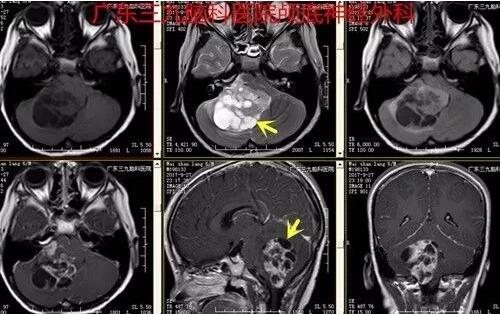

图2:2017-09-27头颅MR示右侧小脑半球一囊实性占位性病变。实性部分呈等T1等T2异常信号影,FLAIR序列呈稍高信号,并间杂小斑片状各序列高信号影,囊性部分呈多发分隔囊状长T1长T2异常信号影,FLAIR序列呈低信号。